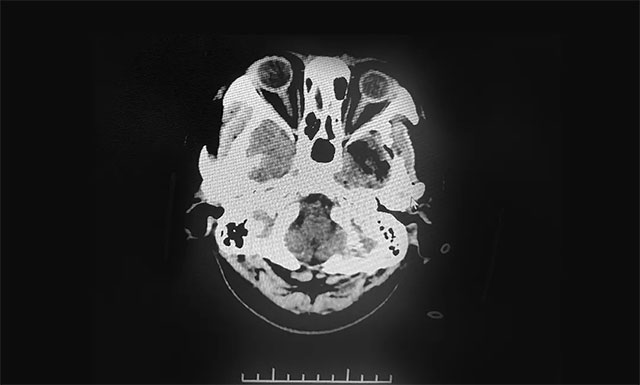

▲ 術后影像顯示腫瘤被切除

術后的病理確診為(硬膜外)神經(jīng)纖維瘤。